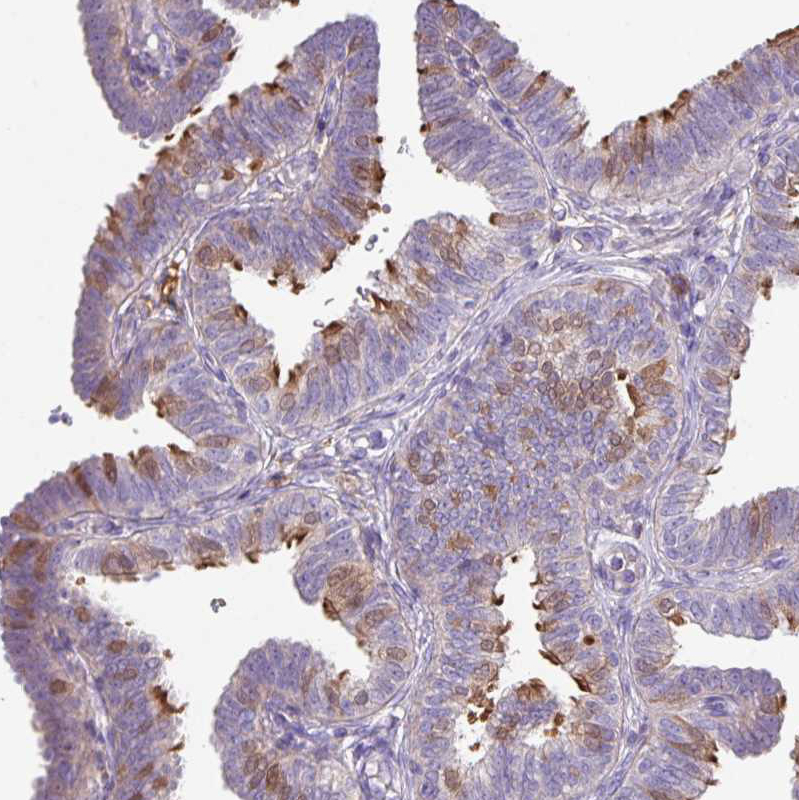

Immunohistochemical staining of human fallopian tube shows strong positivity in cilia in glandular cells.